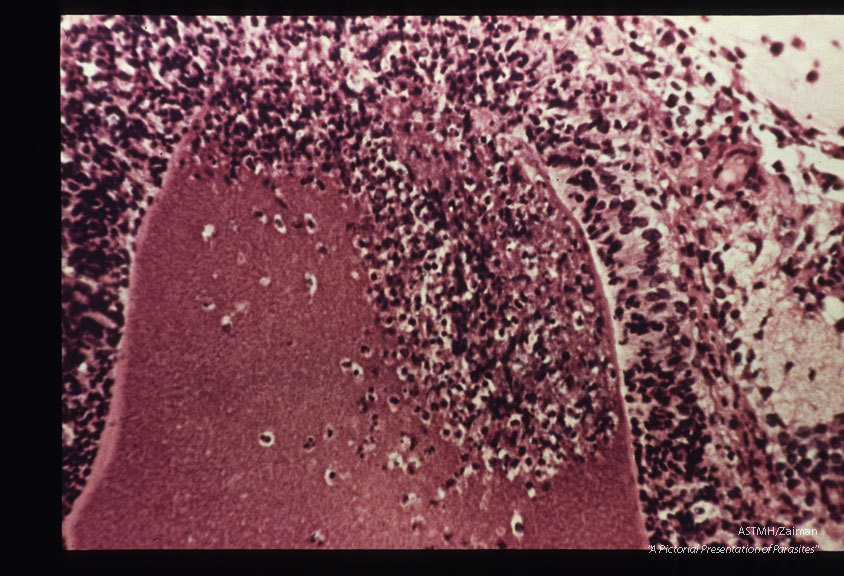

Cyst rupture and retinochoroiditis in hamster. H&E stain.

Besnoitia jellisoni

Description: Cyst rupture and retinochoroiditis in hamster. H&E stain.